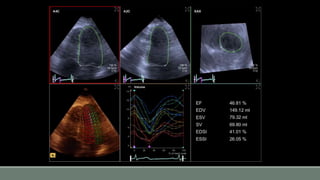

3D live: Thin slice mode

3D live: Zoom mode

3D Imaging: Biplane view

3D FV:

Tomographic slice